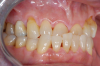

Fig 20. Immediately after extraction and placement.

Figure 20

Occasionally dentists are presented with extreme challenges with long-term restorations and replacing missing teeth. Dentists must evaluate the patient's condition, develop optimum long-term oral health, and attempt to meet the patient's expectations. Figure 18 showed a class III malocclusion with deep bite, multiple abfractions, and less-than-ideal occlusal plane, but the patient wanted to replace his maxillary right canine only. A discussion with the patient regarding occlusal disharmonies and comprehensive recommendations for full-mouth rehabilitation revealed that the patient had a limited budget for dental care. The patient understood the ramifications of his comprehensive dental needs not being affordable. Decisions were made to atraumatically remove the maxillary right canine (Figure 19) and immediately place a ceramic dental implant (Figure 20). Polytetrafluoroethylene (PTFE) 4-0 sutures were placed to help support soft tissues, and then a full-arch Essix-style retainer with a flowable composite facial veneer was used to provide some esthetics during the patient's healing phase (Figure 21). The implant and the retainer were not to be in contactthe retainer may occlude with the opposing dentition and also be passive in relation to the ceramic implant.